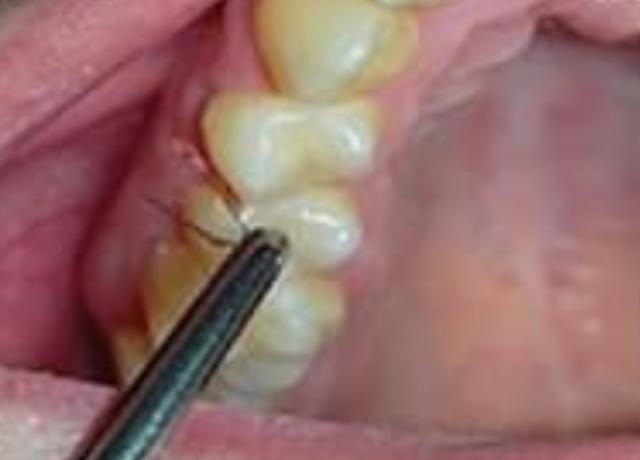

由于未知的原因,她停止了多囊卵巢综合征的治疗,这时她的牙龈多毛症又加重了。这一次,医疗小组不仅摘除了毛发,还从她的牙龈上取下一小块组织,在显微镜下仔细观察。

他们发现一根毛干穿过她牙龈上异常增厚的组织。研究人员说,口腔内的粘膜组织与构成我们皮肤的组织密切相关,因为它们在我们还是胚胎的时候来自同一个地方。

这名妇女的病情恶化了一年,上下两颗牙齿之间的毛发越来越多。目前尚不清楚这名女子是否康复,也不清楚她是否接受了治疗。